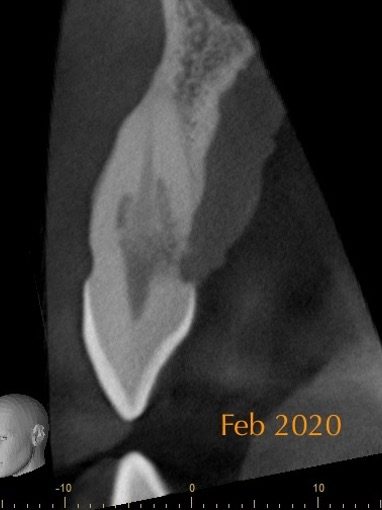

Figure 5: From the PA radiograph LR5 has the classical appearance of internal resorption.

However, the CBCT scan shows the resorption is external cervical resorption.

The resorption starts buccally at the cervical margin. It extends down the root and spreads 360º around the root canal.

We often see this appearance because the canal is surrounded by a protective predentine layer, which is more resistant to resorption